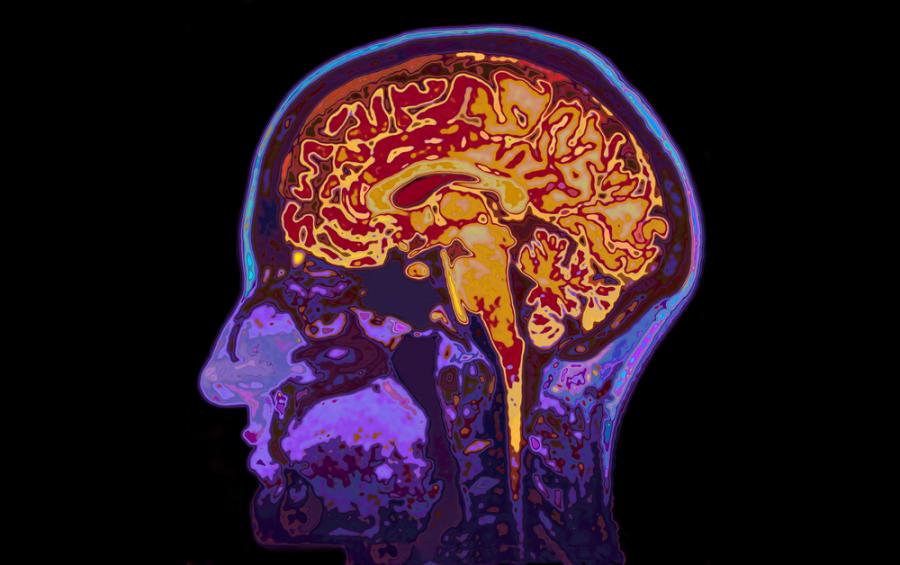

При болестта на Алцхаймер два ключови белтъка - тау и амилоид бета, се натрупват в заплитания и плаки, известни заедно като агрегати, които убиват мозъчните клетки и водят до свиване на мозъка.